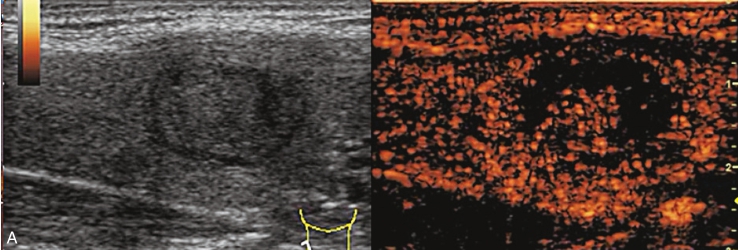

女性,73岁,发现颈部肿胀1个月,伴多汗、心悸、睡眠不佳。甲状腺功能检查:FT3 8.21nmol/L,FT4 20.14nmol/L,TSH 0.001 1μIU/ml。 131 I核素扫描结果提示高功能腺瘤。

甲状腺大小形态失常,左叶增大。甲状腺左叶内见一个等回声结节,边界清楚,形态规则,内部呈均匀等回声,纵横比<1,结节内未见钙化,后方回声无明显变化。CDFI显示结节内有丰富的血流信号,以周边供血为主,见图1-3-26。

图1-3-26 甲状腺高功能腺瘤常规超声表现

A.甲状腺左叶等回声结节纵切面灰阶超声图像;B.甲状腺左叶等回声结节CDFI图像

图像描述:甲状腺左叶结节增强早期呈周边环状增强,向中央逐渐扩张,增强晚期呈均匀稍高增强,见图1-3-27。

图1-3-27 甲状腺高功能腺瘤超声造影图像